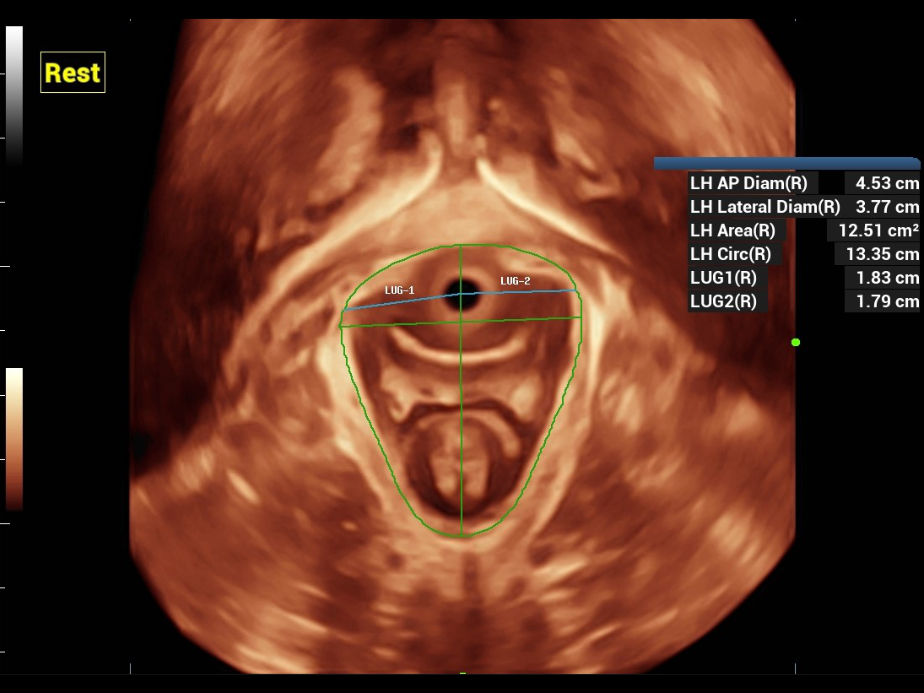

Nuewa bietet automatische 2D-Vermessungen der Beckenabschnitte sowie ein intelligentes Volumenberechnungssystem, einschlie?lich automatisierter Berechnung des Hiatus Levatorius und der Analyse mehrerer Abschnitte.